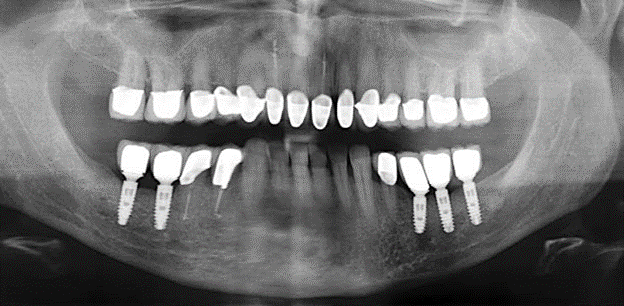

Fig. 1: Panoramic radiograph of initial situation in 2004.

Description of patient case

A 52-year-old patient presented in our clinic for the first time in 2004 following tooth loss in the third quadrant, expressing a desire for a new prosthetic restoration. Periodontal and radiological diagnostics revealed the need for extensive periodontological treatment. In addition, teeth 48, 28 and 27 were attributed a very poor prognosis and were subsequently extracted (Fig. 1). Following the successfully completed, systematic periodontological treatment, a fixed dental implant was inserted with the introduction of five implants in tooth regions 35, 36, 37, 46 and 47. Prosthetic treatment of the natural teeth was effected with veneered zirconium dioxide ceramic crowns; the implants were composed of two-piece, individual zirconium dioxide abutments and similarly veneered crowns made of a zirconium dioxide ceramic (Cercon base colored, Dentsply Sirona Lab). Definitive insertion of the prosthetic restoration occurred in 2005.

The ten-year check-up revealed no indications of advancing clinical attachment loss or peri-implant bone substance loss (Fig. 3).

Fig. 3: Panoramic radiograph after ten years with implants.